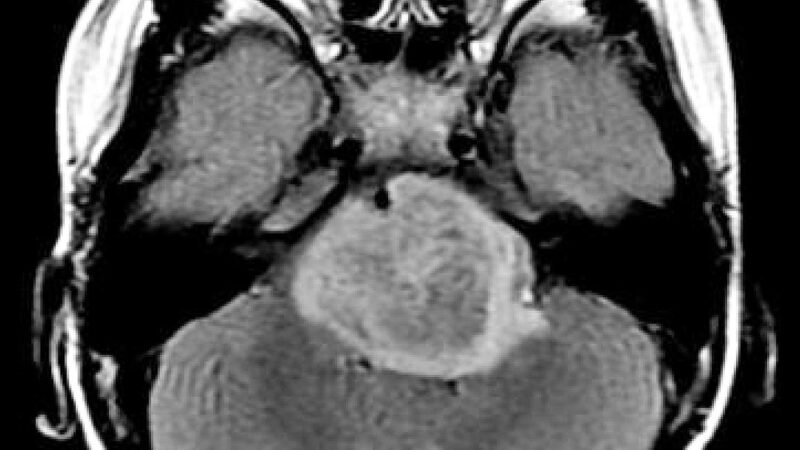

Crédito: Jon Han. Para un puñado de pacientes afortunados, el 2016 ha sido…

Antonio Regalado05/01/2017